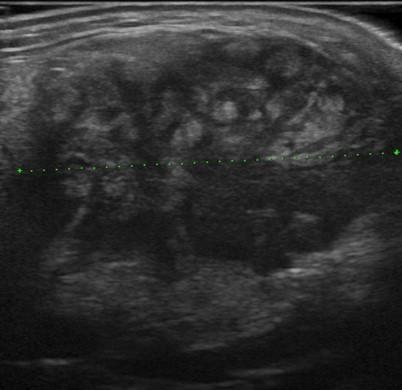

U tuyến nước bọt

U tuyến nước bọt - Ảnh 3

» Thông tin: Nam giới – 83 tuổi.

» Lâm sàng: Khối vùng mang tai.

# Ung thư biểu mô tuyến (Adenocarcinoma).